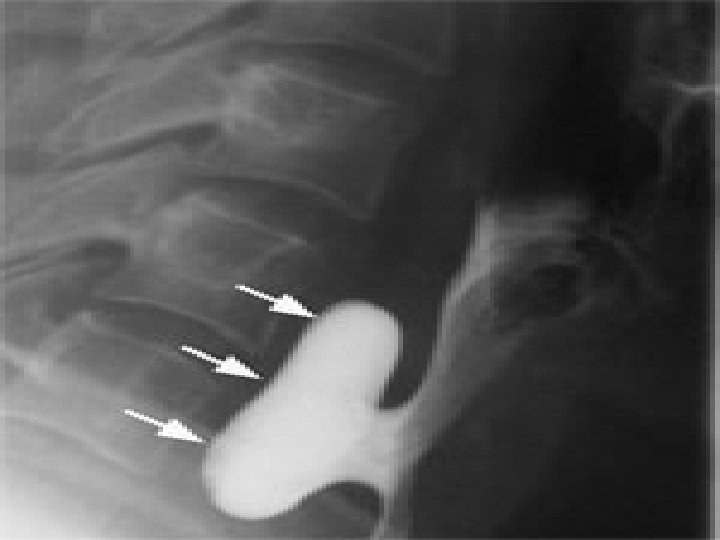

Zenker diverticula occur in a muscular dehiscence that is present most commonly between the oblique muscle fibers of the inferior constrictor muscle and the transverse fibers of the cricopharyngeus (CP) muscle. This area is known as the Killian triangle. � Other areas of muscular dehiscence occur between the oblique and transverse fibers of the CP muscle (ie, Killian-Jamieson area) and between the CP muscle and the esophageal muscles (ie, Laimer triangle). � More inferiorly positioned Zenker diverticula may occur in one of these latter sites �

� Zenker diverticula extend into the left neck 90% of the time. � This is likely due to the slight convexity of the cervical esophagus to the left side and to the more laterally positioned carotid artery on the left side, creating a potential space for the sac.

� � � The combination of the following symptoms is nearly pathognomonic for Zenker diverticulum: Dysphagia Regurgitation of undigested food hours after eating Sensation of food sticking in the throat Special maneuvers to dislodge food Coughing after eating Aspiration of organic material Unexplained weight loss Fetor ex ore Borborygmi in the neck Symptoms may last from months to years. The most common life-threatening complication is aspiration. Other complications include massive bleeding from the mucosa or from fistulization into a major vessel, esophageal obstruction, and fistulization into the trachea. Squamous cell carcinoma (SCC) within Zenker diverticulum is extremely rare, occurring in 0. 3% of Zenker diverticula worldwide. A Mayo Clinic review suggests an incidence of 0. 48% in the United States. Approximately 50 cases of invasive SCC and carcinoma in situ are reported in the literature. This possibility should be considered when evaluating patients with cervical metastatic SCC with an unknown primary cancer.

Zenker diverticula require intervention only if they produce symptoms. In general, small (ie, <2 cm) lesions found incidentally require no intervention. � Small lesions are satisfactorily treated with a CP myotomy with or without an invagination procedure. � Intermediate and large diverticula (ie, 2 -6 cm) are best managed by open diverticulectomy with CP myotomy or by endoscopic diverticulotomy. � Very large diverticula (ie, >6 cm) are best managed with excision with CP myotomy or a diverticulopexy with CP myotomy, depending on the health of the patient �